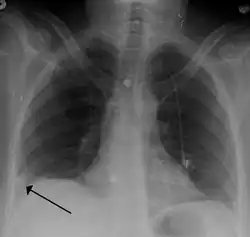

-

Pulmonary embolism (white arrow) that has been long-standing and has caused a lung infarction (black arrow) seen as a reverse halo sign

- Chest X-rays are often done on people with shortness of breath to help rule out other causes, such as congestive heart failure and rib fracture. Chest X-rays in PE are rarely normal,[70] but usually lack signs that suggest the diagnosis of PE (for example, Westermark sign, Hampton's hump).